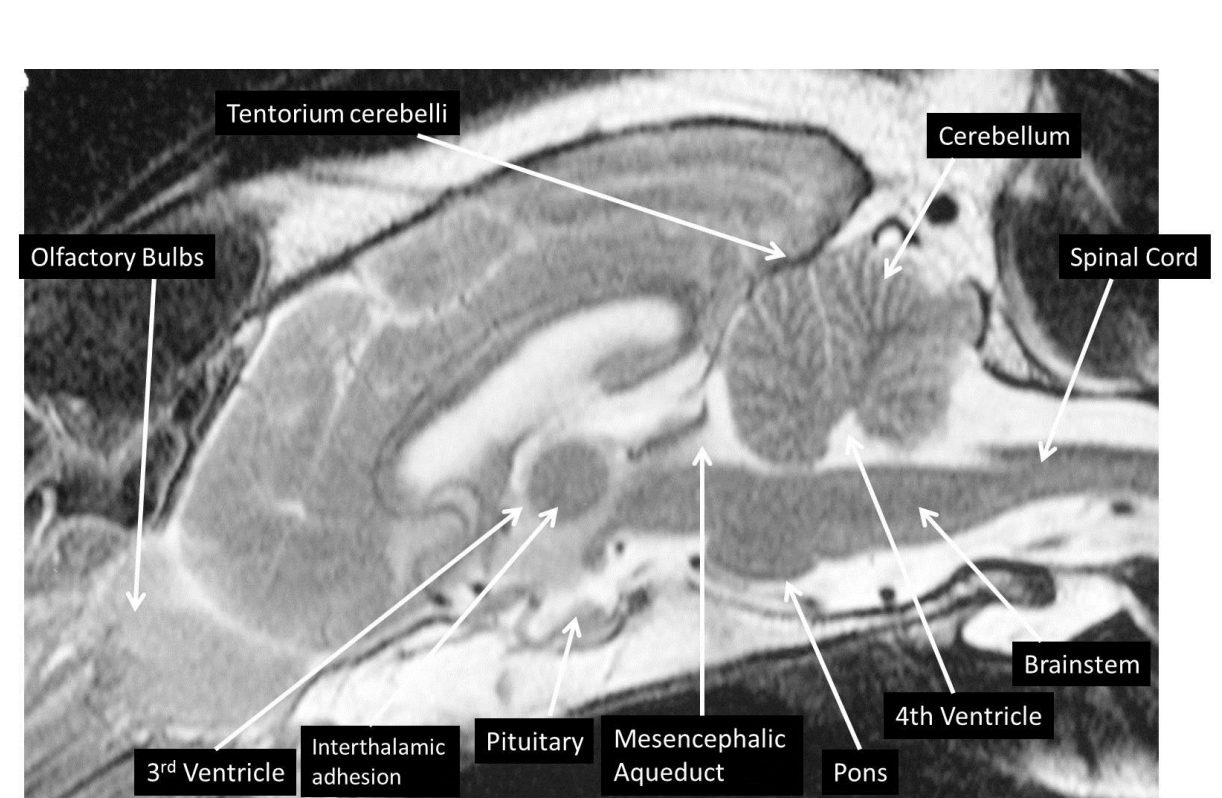

identify the structures

blue: interthalamic adhesion

red: brain stem

silver: spinal cord

identifty the interthalamic adhesion, brain stem, spinal cord